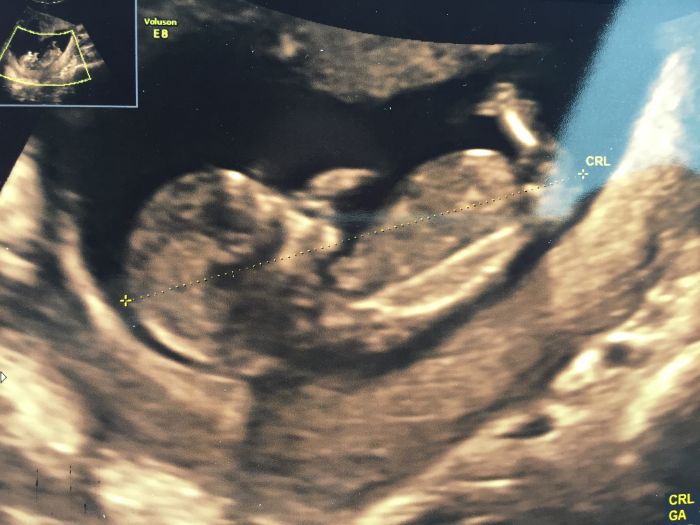

Ahoj holky, to mě mrzí že vás trápí špinění a krvácení, hlavně ať je všechno v pořádku. Ale když doktor říká že to miminko neohrozí tak určitě :) Já už mám za sebou 1.velký UTZ na screeningu a dopadli jsme dobře. Zatím vypadá vše v pořádku a bylo to i příjemné. Šel tam semnou manžel, takže už prcka taky konečně viděl. Celého ho měřila, kontrolovala a ptali se nás na nemoci v rodině, jestli kouřím atd. a pak udělali výpočet s mým věkem. Když potřebovala aby ležel na zádech tak zrovna ani prd, no nasmáli jsme se. Byl zrovna hrozně akční, samá noha samá ruka. Obrázek máme, ale jak se pořád vrtěl tak nebyla šance udělat lepší :D Jinak má teď 6cm. Pohlaví je prý zrovna na hraně vývinu, takže to ještě vidět nebylo. Akorát nás teda ve 20.týdnu čeká s 2. UTZ ještě i konzultace, protože měl manžel v dětství šelest na srdci. Tak si chce dětský doktor prcka taky zkontrolovat.

Ahoj holky. Tak i my máme za sebou dneska 1 screening. Vše vypadá v pořádku, ještě zítra odpoledne budou výsledky z krve. Termín se mi posunul na 10.4.takze jsem ve 14tt. Prcek má skoro 7cm a doktor říkal že to vypadá na holčičku. Mám radost, spadl mi kámen ze srdce. Měla sem z toho vyšetření strach a taky kontrola po 4 týdnech a je to doba když člověk nevím co se tam dole deje když ještě nejsou cítit pohyby. Jinak gratuluji všem to zasebou už taky máte screening a všem co to čeká držím pěsti ;))